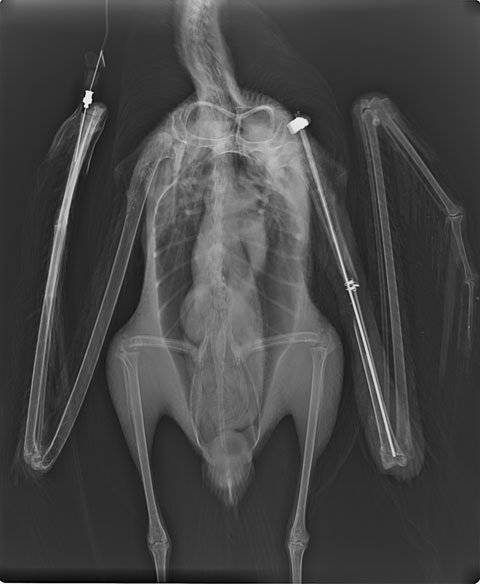

8月に入り、浜中町でコアホウドリが収容されたとの連絡が入りました。診察の結果、左翼の上腕骨が中央にて開放骨折し、骨片の一部は消失していました。また、両足裏に骨が露出するほどの褥瘡があり、飛べずに陸上にいた時間が長かったことが窺えました。極度に衰弱していたため、まずは体力を回復させてから手術を行うことにしました。

状態が回復してきたので、骨折部の整復手術を行いました。離断部をつなぐことはできましたが、骨片が大きく消失していたため、正常な骨の長さ通りに癒合してくれるかは難しいところです。コアホウドリを含むアホウドリ類は、鳥の中でもかなりの長距離移動を行う種です。骨同士がついたとしても野外で生きていけるほど飛翔能力が戻るかはわかりません。今は骨折部位が癒合してくれるのを待つばかりです。